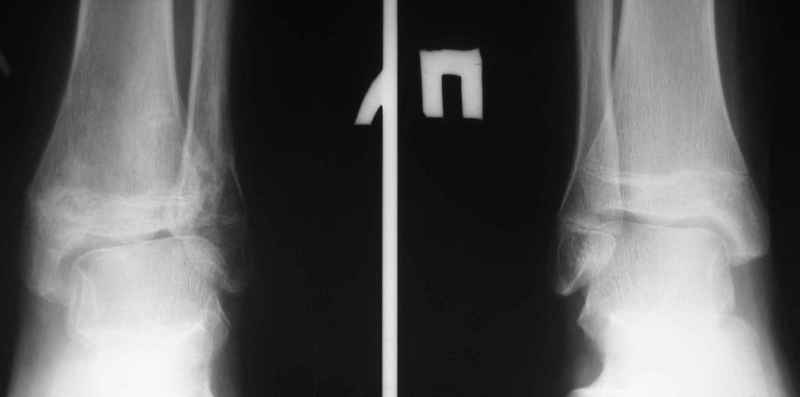

Здравствуйте, коллеги.Обратились родители мальчика 15 лет. Сами врачи.В июле 2009 года - перелом лодыжек.

Лечили спорно, на мой взгляд. В результате - - сращение наружной лодыжки с укорочением, подвывих голеностопа кнаружи (вальгус) в итоге компенсаторно передний отдел стопы ставит на варус. Нагрузку ограничивает.

Снимки в приложении.